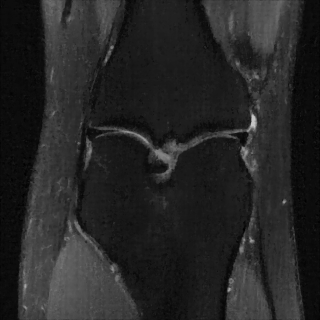

This article presents a novel undersampled magnetic resonance imaging (MRI) technique that leverages the concept of Neural Radiance Field (NeRF). With radial undersampling, the corresponding imaging problem can be reformulated into an image modeling task from sparse-view rendered data; therefore, a high dimensional MR image is obtainable from undersampled $k$-space data by taking advantage of implicit neural representation. A multi-layer perceptron, which is designed to output an image intensity from a spatial coordinate, learns the MR physics-driven rendering relation between given measurement data and desired image. Effective undersampling strategies for high-quality neural representation are investigated. The proposed method serves two benefits: (i) The learning is based fully on single undersampled $k$-space data, not a bunch of measured data and target image sets. It can be used potentially for diagnostic MR imaging, such as fetal MRI, where data acquisition is relatively rare or limited against diversity of clinical images while undersampled reconstruction is highly demanded. (ii) A reconstructed MR image is a scan-specific representation highly adaptive to the given $k$-space measurement. Numerous experiments validate the feasibility and capability of the proposed approach.